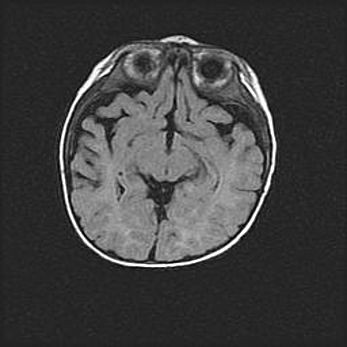

Церебральная ишемия II.

Возраст: 5 дней

Вес: 3400 г

Пол: женский

Окружность головы: 35 см

Срок гестации: 39 недель

Церебральная ишемия – это заболевание, характеризующееся недостаточностью (гипоксией) либо полным прекращением (аноксией) снабжения мозга кислородом по причине закупорки одного или нескольких сосудов. Это приводит к  что метаболическим расстройствам различной степени тяжести в тканях головного мозга, развитию коагуляционных некрозов и гибели нейронов.